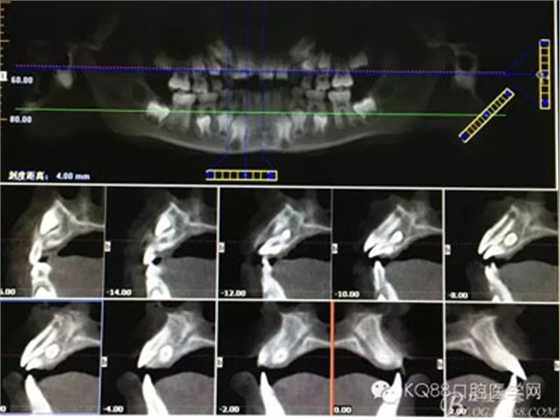

圖3.根據(jù)臨床檢查,做CBCT影像檢查:11與21之間有一倒置多生牙,多生牙牙根位于11與21之間,牙冠位于11與12之間。